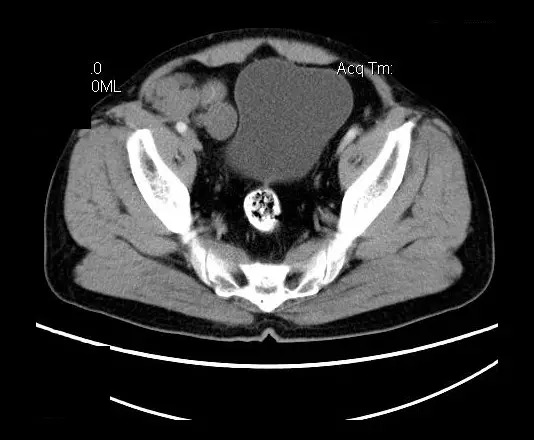

【影像表现】

盆腔右前侧及邻近腹股沟区可见多发大小不等的聚集生长的结节影,病灶呈软组织密度,边缘尚规整,分界尚清,增强扫描可见不均匀强化。膀胱局部受压,盆腔未见明显肿大淋巴结影。

“盆腔”多发性神经鞘瘤

平扫影像表现:Antoni A区较多病灶,在CT上呈等或略高密度影,T1WI等信号、T2WI略高信号,AntoniB区较多病灶,CT多为水样低密度、T1WI低信号、T2WI明显高信号。

增强影像表现:神经鞘膜肿瘤增强后,由于Antoni A区与B区以不同比例混合而强化不一,呈不均匀斑片状,条状强化。Antoni A 区富血供,中等或明显强化,Antoni B区乏血供,强化多不明显。